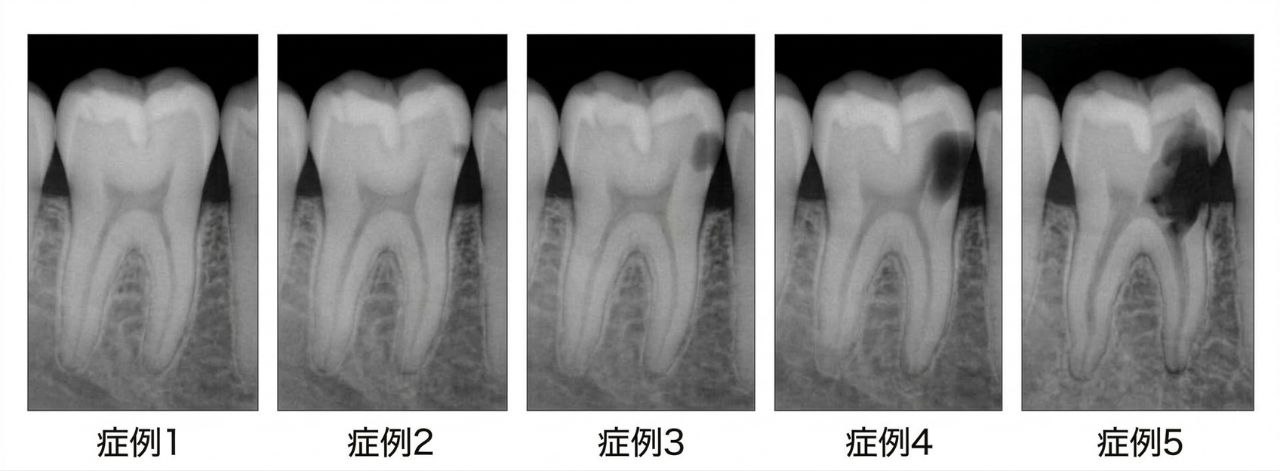

症例1〜2:経過観察 / 症例3:要精査 / 症例4〜5:修復推奨(概念図)

① 象牙質の外1/3(D1)を超えた深さの虫歯

X線写真で象牙質の外側1/3を超えて進んでいると判断される場合は、介入が推奨されます。